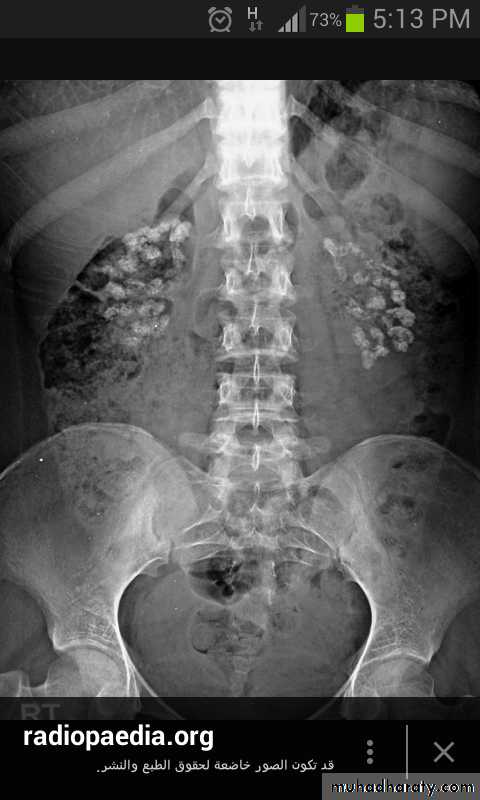

Nephrocalcinosis

Skeletal X-rays:Normal in early disease

Demineralization

Subperiosteal erosions and terminal resorption of phalanges

Osteopenia and osteoporosis by DEXA